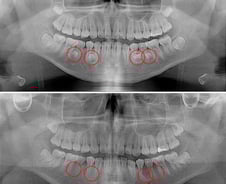

20대 김호영(가명) 씨는 어린 시절부터 치아가 고르지 못하고 자주 잇몸이 붓는 등 구강 건강이 좋지 않았다. 다들 그러려니 하며 대수롭지 않게 생각했지만, 몇 년 전 치과 X선 촬영에서 치아가 많은 '과잉치'를 진단받았다. 시간이 지나면서 치아 배열이 점점 더 불규칙해지고 지금은 음식을 씹는 것조차 어려움을 겪고 있다. 일반적으로 사람의 구강에는 28개의 영구치와 4개의 사랑니가 나와 총 32개의 치아가 자란다. 이보다 더 많거나, 불필요한 치아가 추가로 생기는 경우를 과잉치라 한다. 정확한 원인은 밝혀지지 않았지만 부모나 형제에게 과잉치가 있으면 발생 확률이 높아지는 것으로 보고된다. 대부분 턱뼈 내에 매복돼 있어 보호자는 물론 당사자조차 모르는 경우가 많다. 과잉치는 '구강 내 시한폭탄'으로 비유될 만큼 다양한 구강 문제를 일으킨다. 치아의 정상적인 맹출(치아가 잇몸 속에서부터 잇몸을 뚫고 올라오는) 과정을 방해하기 때문이다. 특히 영구치가 자리 잡는 6~15세 사이에는 더욱